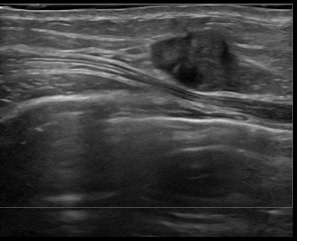

상기환자는 우측 만져지는 멍울,외부검사이상소견으로 내원하신 50대중반

여성분으로 의심스러운 우측혹 조직검사 시행해 침윤성암으로 진단되었습니다